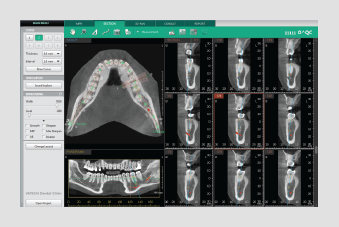

Powered by a new 3D VR graphics engine, the Ez3D-i is the ideal tool to effortlessly obtain the correct perspectives needed for accurate and true-to-measurement diagnosis.

• Various VR coloring modes and 2D filters

• Intuitive implant simulation tools for collision detection (implant/canal), bone density verification, and oblique viewing tools

• 3D panoramic navigation

• Multiple sectional curves and segmentation tools

• 3D panorama

• Teeth mode

• Bone mode

• Soft-tissue bone mode

• MIP mode

• Soft-tissue mode

Quickly and easily switch between multiple VR views

SECTION TAB

3D PAN TAB

• Draw sectional curves from either the MPR View or Sectional View

• Easily manage up to 8 different sectional curves

• Intuitive click-and-drag sectional view manipulation